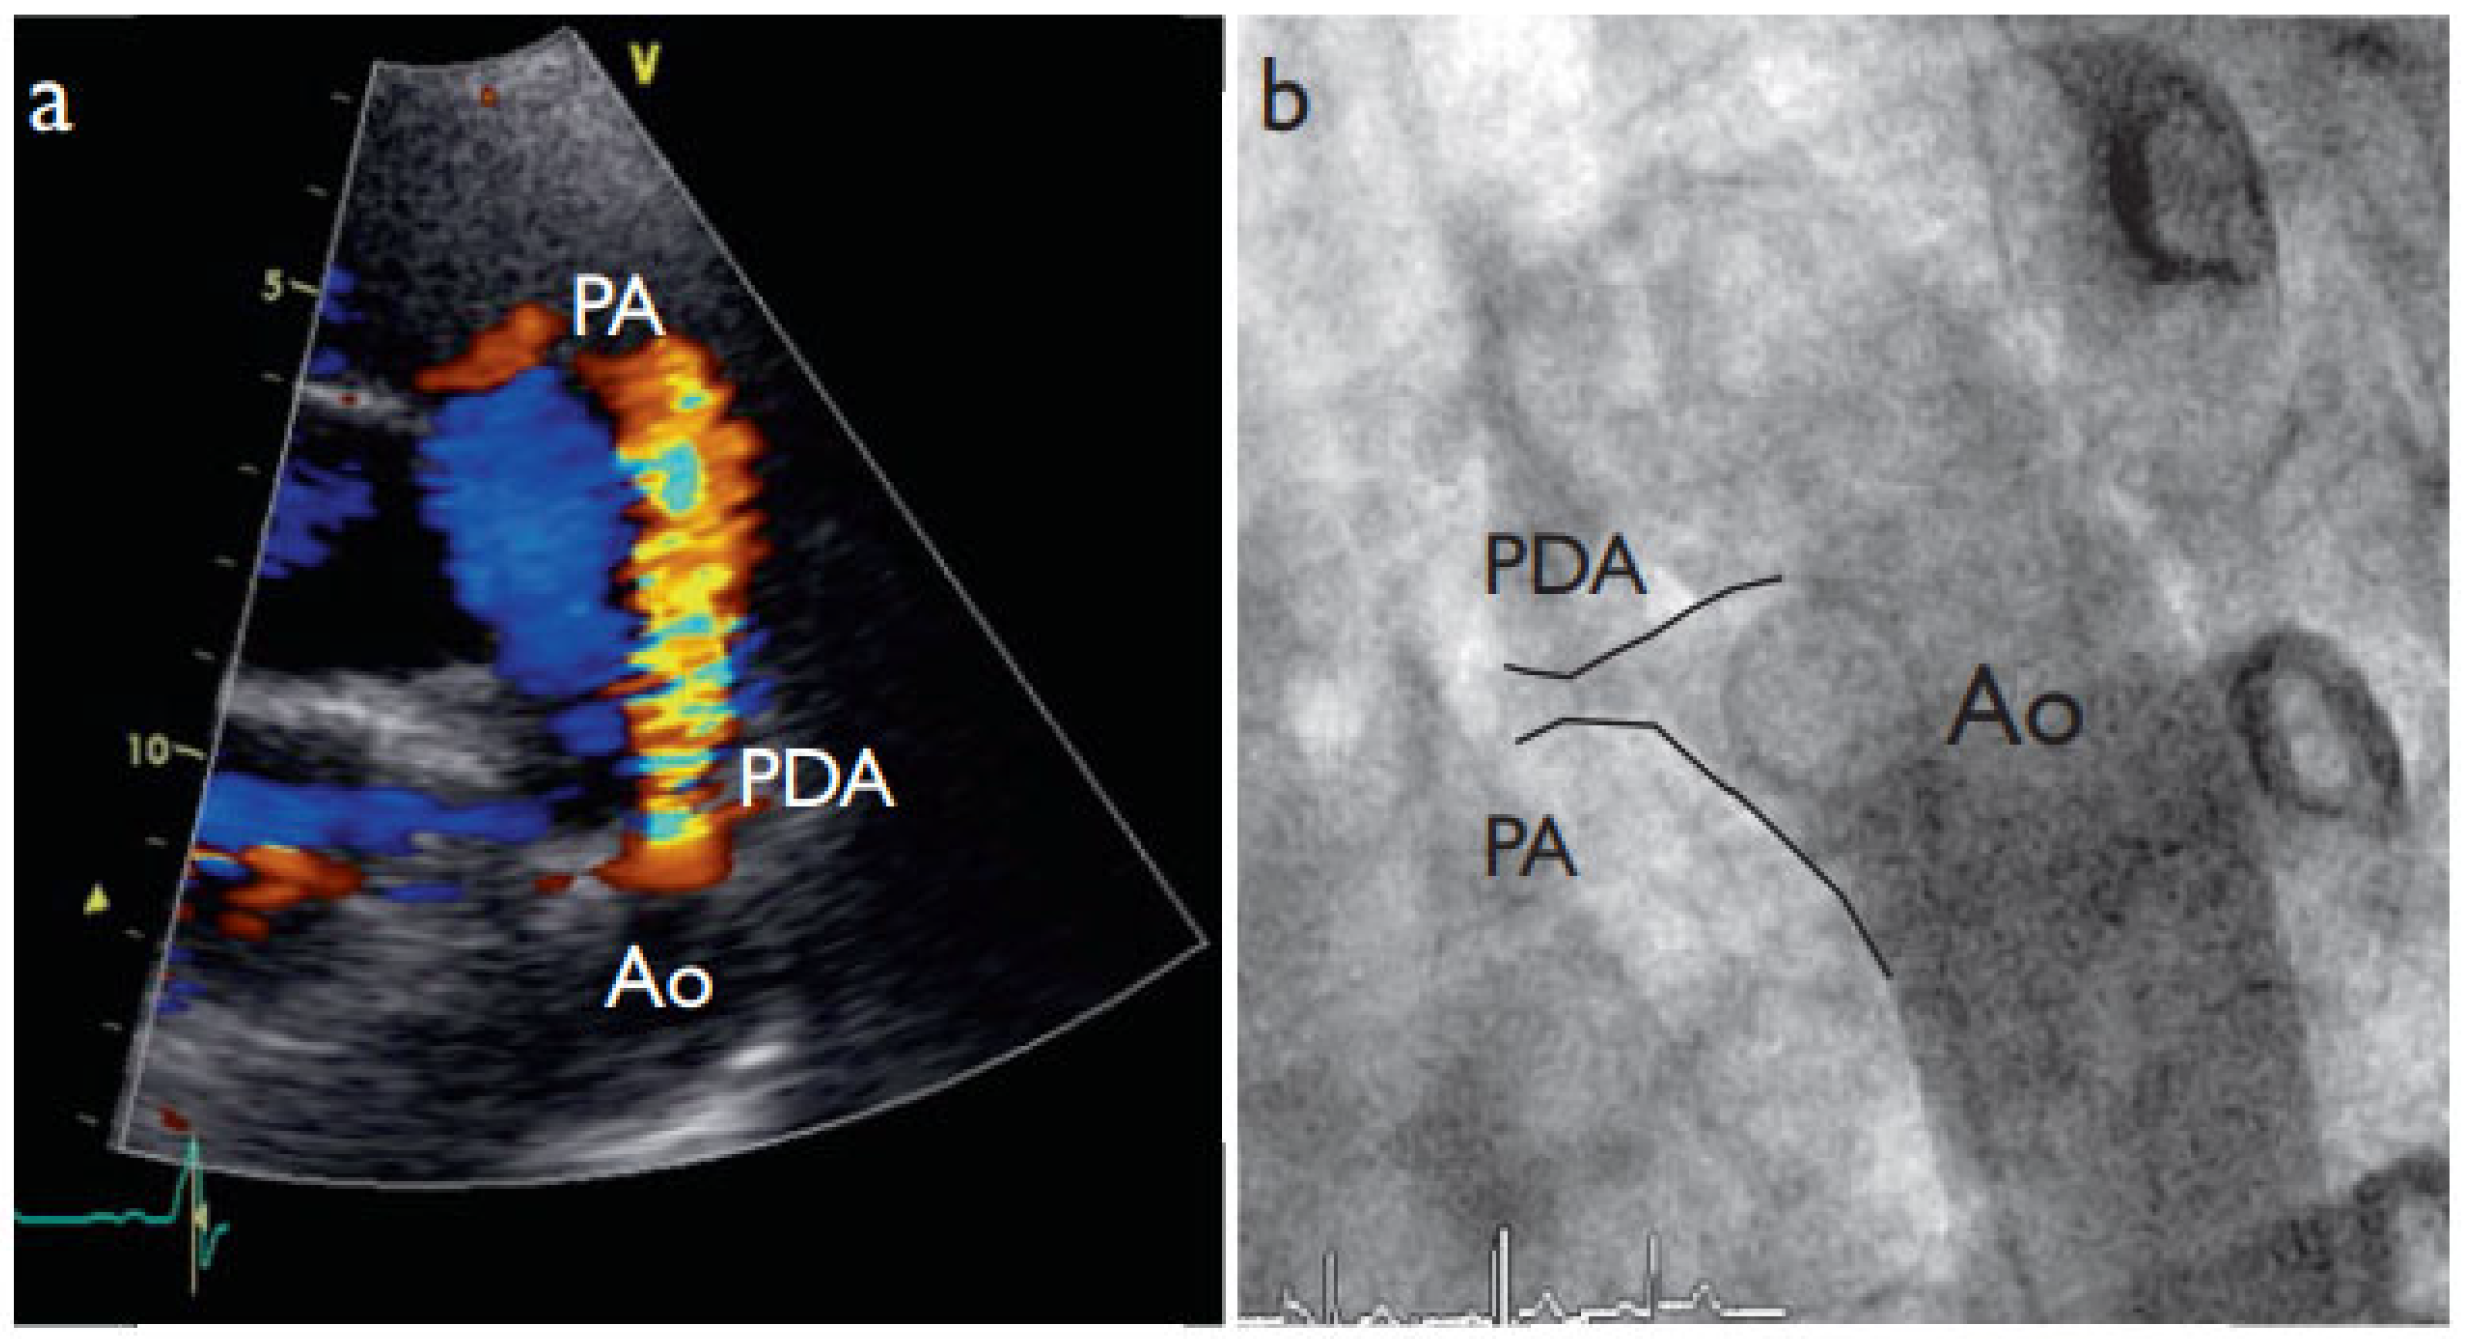

A 28-year-old female patient presented for investigation of a continuous heart murmur. Echocardiography revealed a left-to-right shunt through a patent ductus arteriosus (Figure 1a) and the patient was referred for outpatient percutaneous closure.

Figure 1. a) Parasternal short axis echocardiographic view of the aortic valve showing the right ventricular outflow tract and the pulmonary main artery (PA). Colour flow imaging of systolic left-to-right shunt (red) through the patent ductus arteriosus (PDA), and b) subsequent confirmation of diagnosis by aortography (4 French pigtail catheter in descending aorta, Ao).